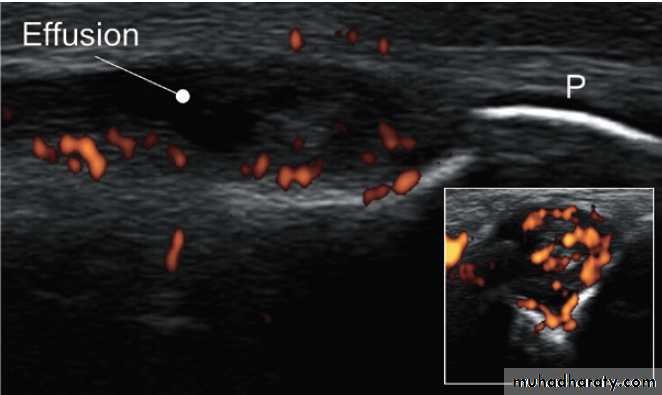

Ultrasonography

Ultrasonography is a useful investigation for confirmationof small joint synovitis and erosion, for anatomical

confirmation of periarticular lesions, and for guided

aspiration and injection of joints and bursae. Ultrasound

is more sensitive than clinical examination for the

detection of early synovitis and is used increasingly

in the diagnosis and assessment of patients with suspected

inflammatory arthritis. In addition to locating

synovial thickening and effusions, ultrasound can detect

increased blood flow within synovium using power

Doppler imaging, an option that is available on most

modern ultrasound machines .

Ultrasound image showing synovitis. Lateral image of a metacarpophalangeal joint in inflammatory arthritis. The periosteum (P) of the phalanx shows as a white line. The dark, hypo-echoic area indicates

an effusion. The coloured areas demonstrated by power Doppler indicate

increased vascularity. The inset shows a transverse image of the same joint.